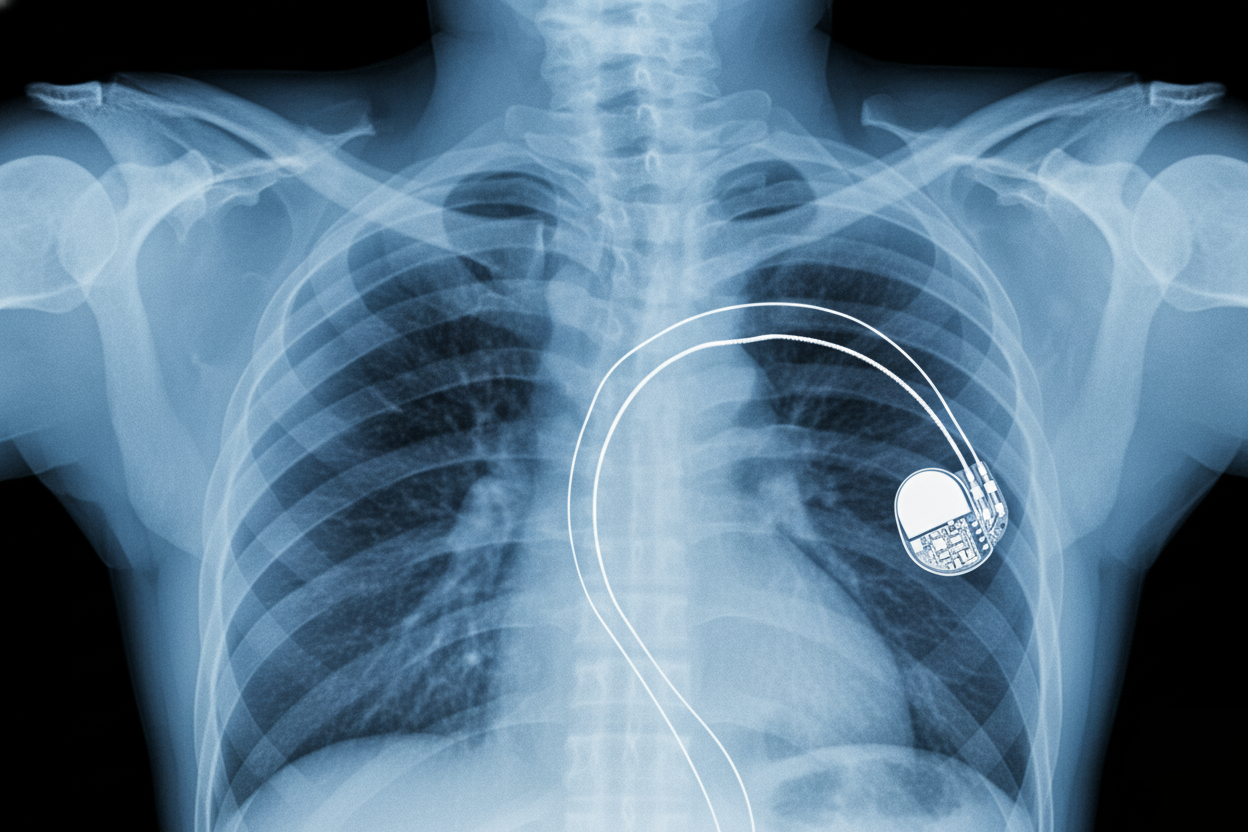

Immaginate un omicidio perfetto. La vittima cede nel sonno, apparentemente per un fatale attacco di cuore. Il medico legale archivia il caso: cause naturali. Nessun veleno, nessuna colluttazione, nessuna impronta. A chilometri di distanza, qualcuno spegne un laptop. Missione compiuta. Questa non è la trama di un film, ma una delle vulnerabilità più intime dell’era moderna: l’assassinio Wi-Fi. Il proiettile? Un dispositivo nato per salvare vite. La minaccia di hackerare un pacemaker è reale.

Per anni, i dispositivi medici come pacemaker, defibrillatori impiantabili (ICD) e pompe di insulina erano sistemi chiusi. Oggi sono “smart”. Possiedono connettività wireless (Radio Frequenza o Bluetooth) per un motivo nobile: i medici possono monitorare i pazienti e regolare i dispositivi da remoto, evitando interventi invasivi. Questa comodità, tuttavia, ha generato una falla catastrofica. Quella connessione è una porta che gli hacker possono forzare.

Un malintenzionato, con le conoscenze giuste e un’antenna specializzata, può intercettare il segnale del dispositivo a distanza. Non è necessario trovarsi nella stessa stanza; a volte basta essere nello stesso edificio o in un’auto parcheggiata. Una volta stabilito il contatto, l’assassino digitale ottiene il controllo totale sul cuore della vittima.